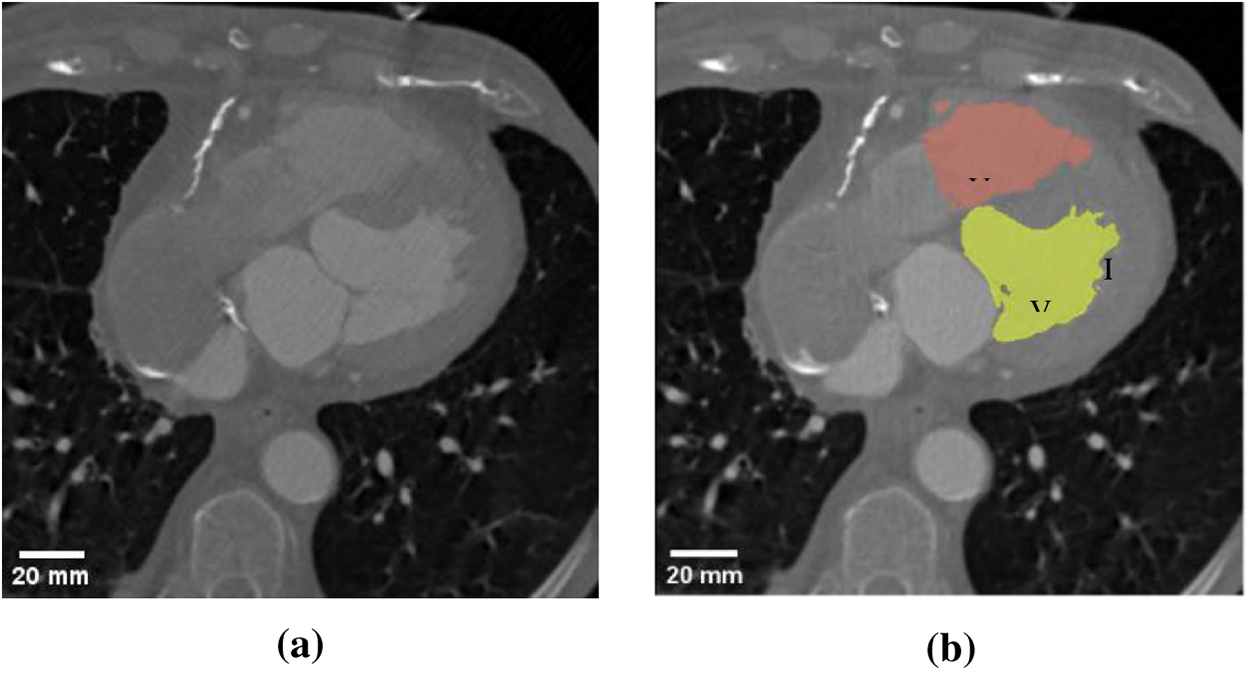

The training dataset comprised 19 Coronary Computed Tomography Angiography (CCTA) scans acquired from patients diagnosed with diverse cardiac pathologies (n = 19). The dataset analyzed in this study is a pre-existing, fully anonymized dataset provided by a third party (MST). All data were de-identified by the provider prior to being accessed by the authors, ensuring that no individual participants can be identified. The data are not publicly available due to privacy. Each scan was associated with a segmentation mask delineating the boundaries of 13 anatomical structures. These masks were initially annotated by medical professionals and subsequently validated by independent clinical experts to ensure ground-truth fidelity. Fig. 1 illustrates representative data, displaying an acquired CCTA scan alongside its corresponding expert-verified segmentation. This integration of high-resolution imaging with precise annotations is intended to capture the significant morphological heterogeneity of ventricular anatomy within the patient cohort. Fig. 2 presents a three-dimensional reconstruction of the ventricles extracted from a single scan, highlighting the geometric complexity modeled in this study.

Figure 1: Representative sample of used data (a) Computed tomography scan; (b) Manual segmentation mask.